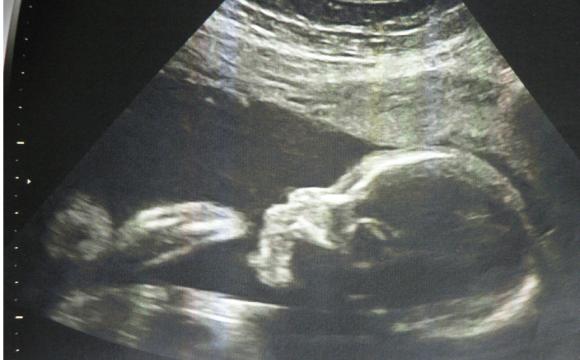

现在胎宝宝身长16~18厘米,重300~500克。这时期,胎儿的体重开始大幅增加,眉毛和眼脸清晰可见,手指和脚趾也开始长出指甲。如果胎儿是个女孩,她的阴道现在已经形成了,并且会继续发育到出生;如果是男孩,*丸睾**将从盆骨降到阴囊内,原始精子已经形成。随着大脑和神经末梢的发育,胎儿的各种感官正在逐步完善,如味蕾开始在舌面上形成。

本周胎儿重350克左右,身长达到了19厘米左右。胎宝宝的脑部开始迅速生长,尤其是位于大脑中心的生发基质,它负责产生脑细胞。胎儿现在看上去滑溜溜的,胎脂覆盖了他的全身。胎脂可以保护胎儿的皮肤,不少胎儿在出生时身上都还残留着这些白色的胎脂。宝宝清醒的时间越来越长,当他清醒时,能够很清楚地听到外面大人的谈话、音乐或噪音。有时孕妈妈轻轻拍打腹部时,他也会被惊醒。

本周胎儿大约重450克,从头到臀长20厘米左右。这时期,胎儿的皮肤薄薄的,红红的,还皱巴巴的,样子像个小老头,但身体比例已经较为匀称。胎儿的嘴唇、眉毛和眼睫毛已清晰可见。宝宝的眼睛已经发育,视网膜也已形成,具备了微弱的视觉。宝宝的嘴唇越来越清晰,在胎儿的牙龈下面,幼小的牙蕾也开始发育了,显露出长牙的最初迹象。

怀孕第24周

本周胎儿身长25-30厘米,体重大约在550克,胎儿的呼吸系统正在发育,不停吞咽羊水来练习呼吸,使肺得到进一步完善。此时宝宝的听力完全形成,他能分辨出孕妈妈发出的说话声音。当然,外界的噪音,如汽车鸣笛、吸尘器等声音也会让胎儿焦躁不安。胎儿在发育身体的同时,也逐步变为有意识的、对感觉有反应的人了,他的外貌和举止已经像出生时的新生儿了。